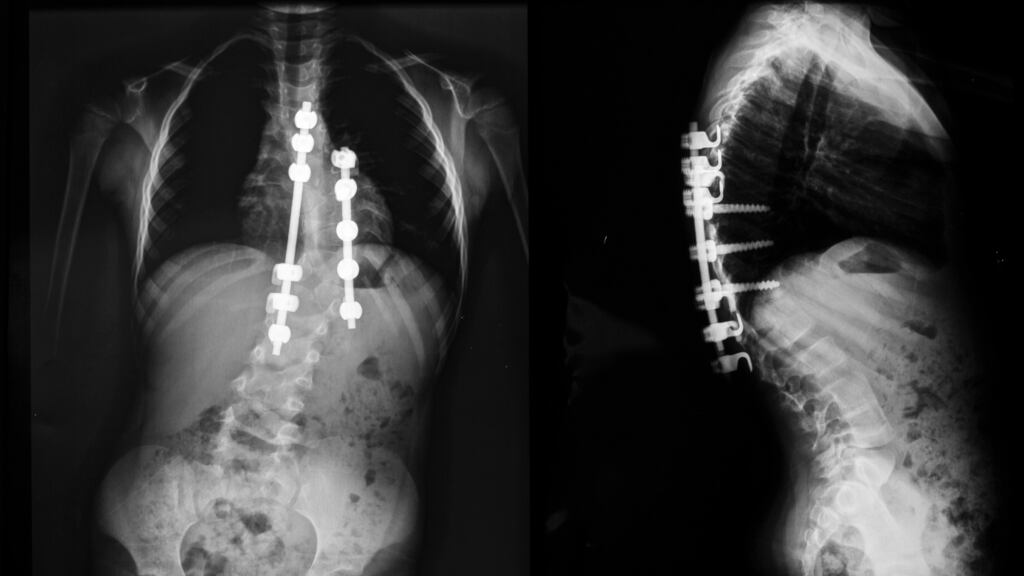

CHI said 32 children with scoliosis were waiting for surgery at Temple Street hospital.

Commenting on the pause in surgeries at Temple Street, CHI said the problem was “due to the cumulative impact of undertaking a greater volume of these complex surgeries in recent months”. It said the volume of cases had “resulted in workload pressures for hospital services in terms of beds and theatre capacity and also for staff working within the service”.

The nature of the surgery means patients have increased medical needs and a likelihood of longer stays in hospital for children and young adults with complex conditions.